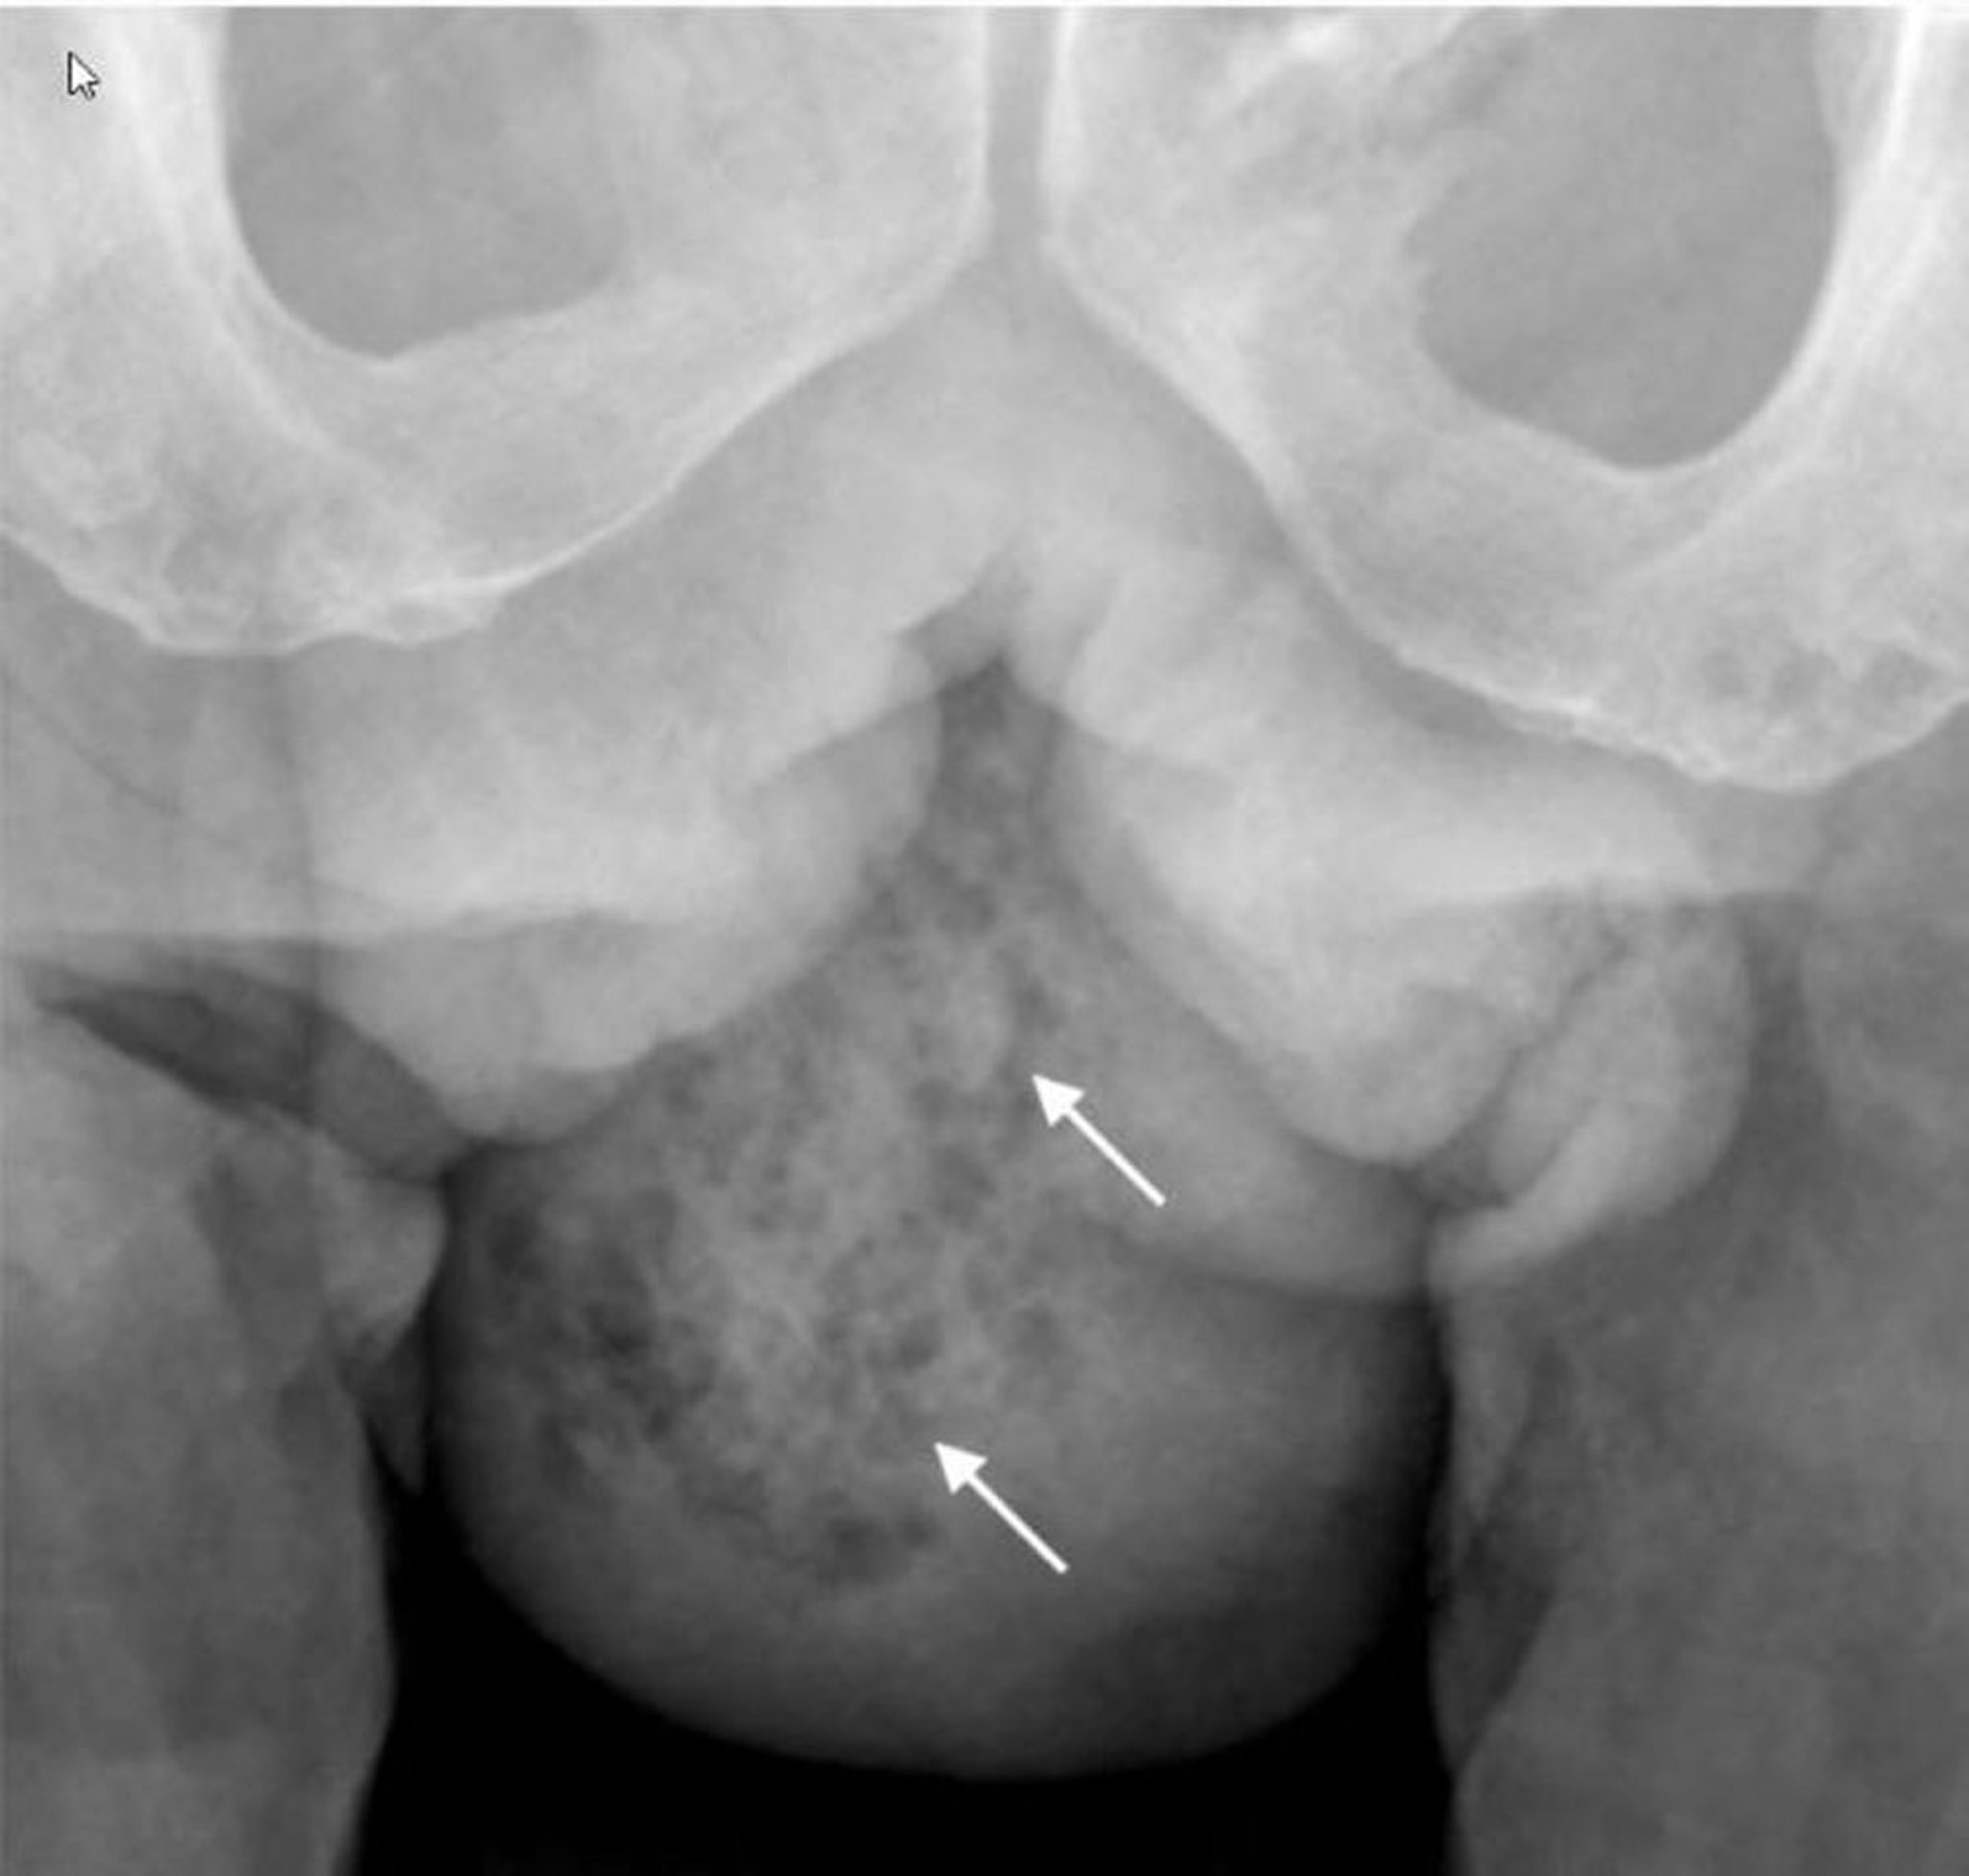

Gangrène de Fournier (radio)

Cette radiographie montre un gaz dans les tissus mous de l'hémiscrotum droit (flèches).